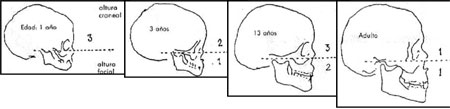

Estas estructuras tienen un crecimiento acelerado durante los primeros cuatro años de vida. En este lapso aumentan espectacularmente de tamaño, sufren una importante remodelación, a la vez que desarrollan una imbricada interrelación funcional de creciente complejidad.

La ontogenia repite en forma sucinta las referencias de la filogenia.

En el recién nacido se inician sus capacidades orales, con las reacciones reflejas de respiración y succión-deglución, y el proceso de adquisición de las diferentes funciones se prolonga hasta alrededor de los 5.-6 años, que es cuando el sistema adquiere un discreto equilibrio. Este proceso ha sido denominado por la escuela francesa, Hominización de la extremidad cefálica, y a lo largo de él, la madre por medio de las cuidados maternales, inicia la formación del núcleo emocional básico del niño.